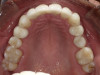

Fig 2. Candidates for hybrid teledentistry include patients with minor (Fig 2), moderate (Fig 3), and advanced crowding (Fig 4).

FIgure 2